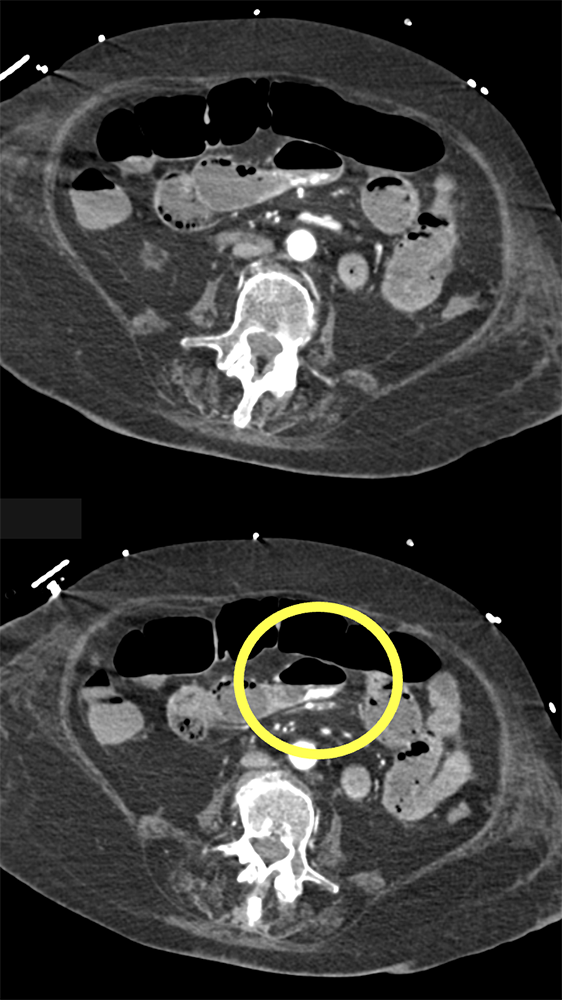

GI Bleed in Patient with Crohn’s and had Atrial Fib on Anticoagulants ![]() |

![]() |